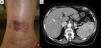

La inmunodeficiencia variable común es una inmunodeficiencia primaria por hipogamaglobulinemia de IgG e IgA poco frecuente en la población. Clásicamente se presenta durante la juventud y se diagnostica durante la investigación de infecciones respiratorias y gastrointestinales a repetición. Estos pacientes pueden además presentar enfermedades autoinmunes, inflamatorias, neoplásicas, malabsorción y problemas granulomatosos no infecciosos, que afectan el pulmón, ganglios, bazo, hígado, y menos usualmente la piel. Presentamos el caso de una paciente diagnosticada de inmunodeficiencia variable común que se presenta en la consulta dermatológica con múltiples nódulos eritemato-costrosos en miembros, donde se hallaron únicamente granulomas asépticos.

Common variable immunodeficiency is a rare, primary immunodeficiency characterized by hypogammaglobulinemia of IgG and IgA. It classically presents as recurrent respiratory and gastrointestinal infections in young patients, who may also have autoimmune and inflammatory disease, malignancies, malabsorption and non-infectious granulomas, mainly located in the lung, lymph nodes, spleen, liver and, less frequently, in the skin. We report the case of a patient diagnosed with common variable immunodeficiency who presented in the dermatology clinic with multiple, erythematous, crusted nodules on the limbs. Only aseptic granulomas were found.